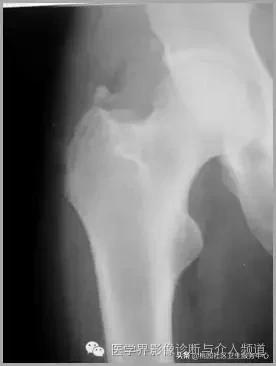

六、肌腱钙化/滑囊炎并钙化

肩关节最常见:肱二头肌长头、肩峰下滑囊钙化,可伴有急性疼痛、肿胀,局部压痛。

大粗隆滑囊炎